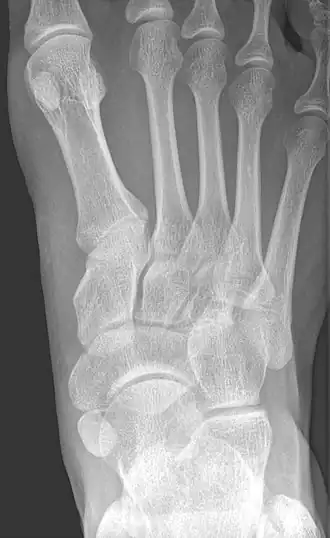

Radiological images

Type 2 -